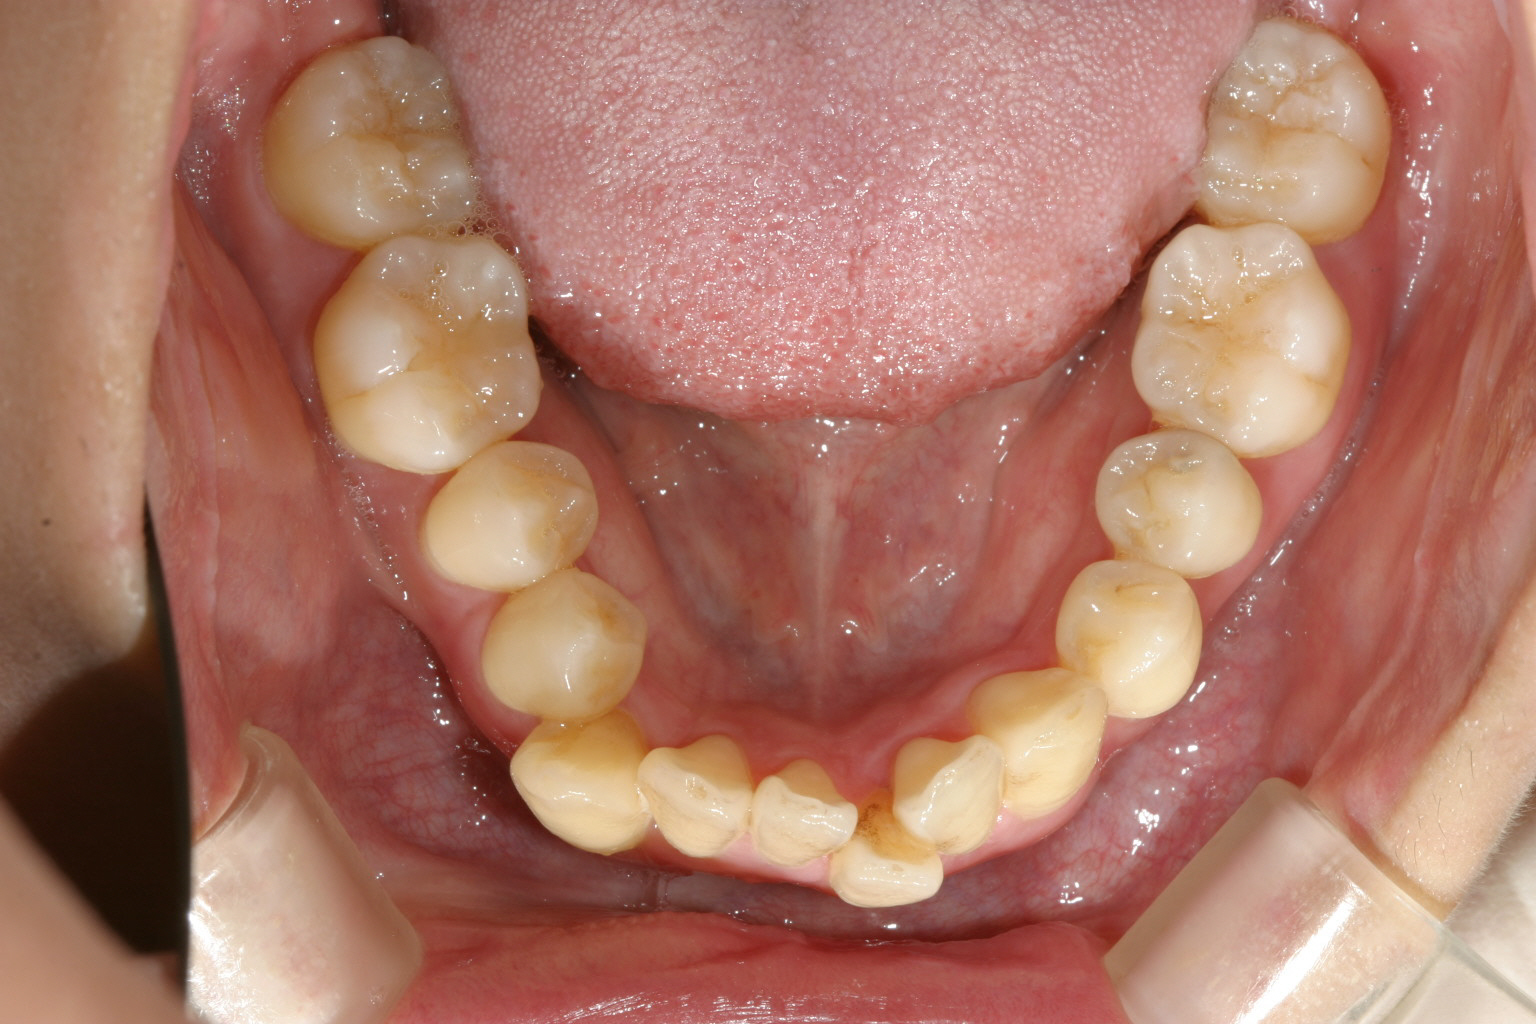

下顎前歯の叢生もかなりのもんです。 と言う事でワイヤー矯正を選択しました。

下顎のアーチも綺麗です。